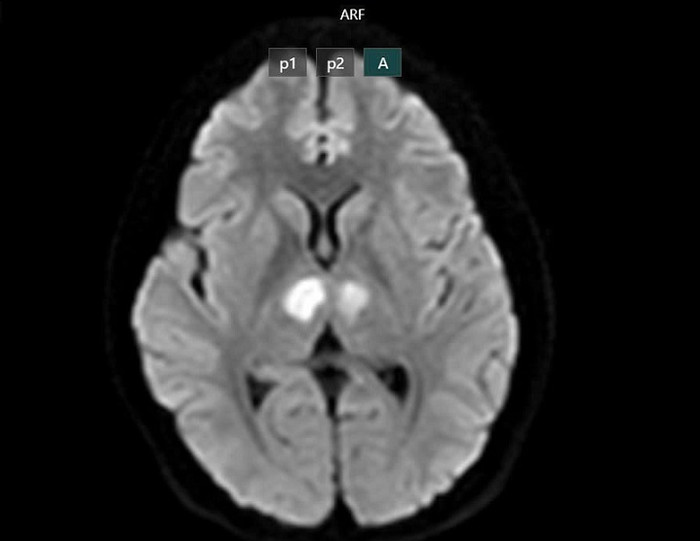

Kết quả chụp MRI cho thấy não bệnh nhân có hình ảnh tổn thương vùng đồi thị hai bên. Gia đình xin chuyển bệnh nhân sang Bệnh viện Bạch Mai để được tiếp tục điều trị.

Phim chụp cho thấy não bệnh nhân bị tổn thương vùng đồi thị hai bên. Ảnh: BVCC